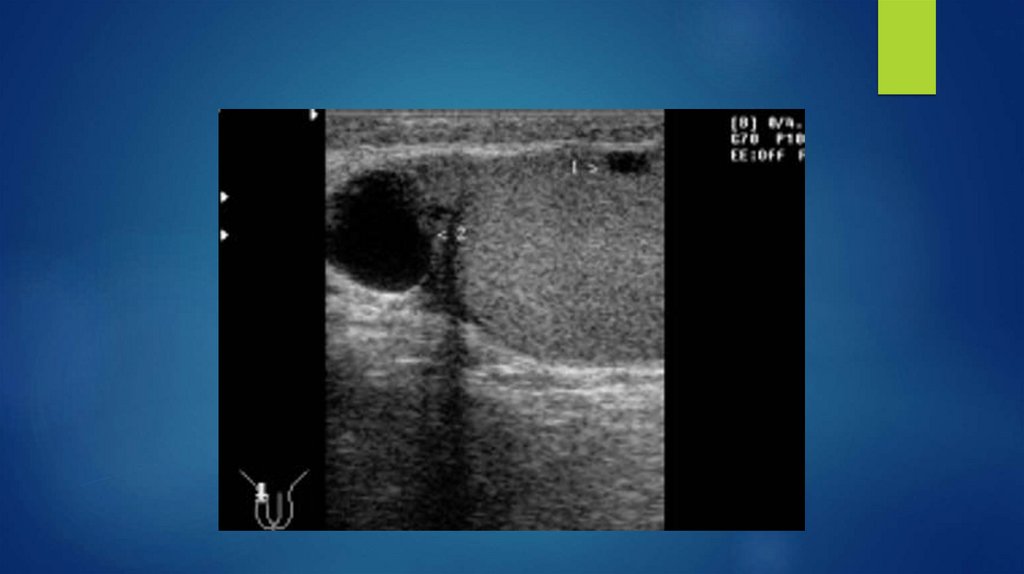

13. Киста почки

14. Киста почки